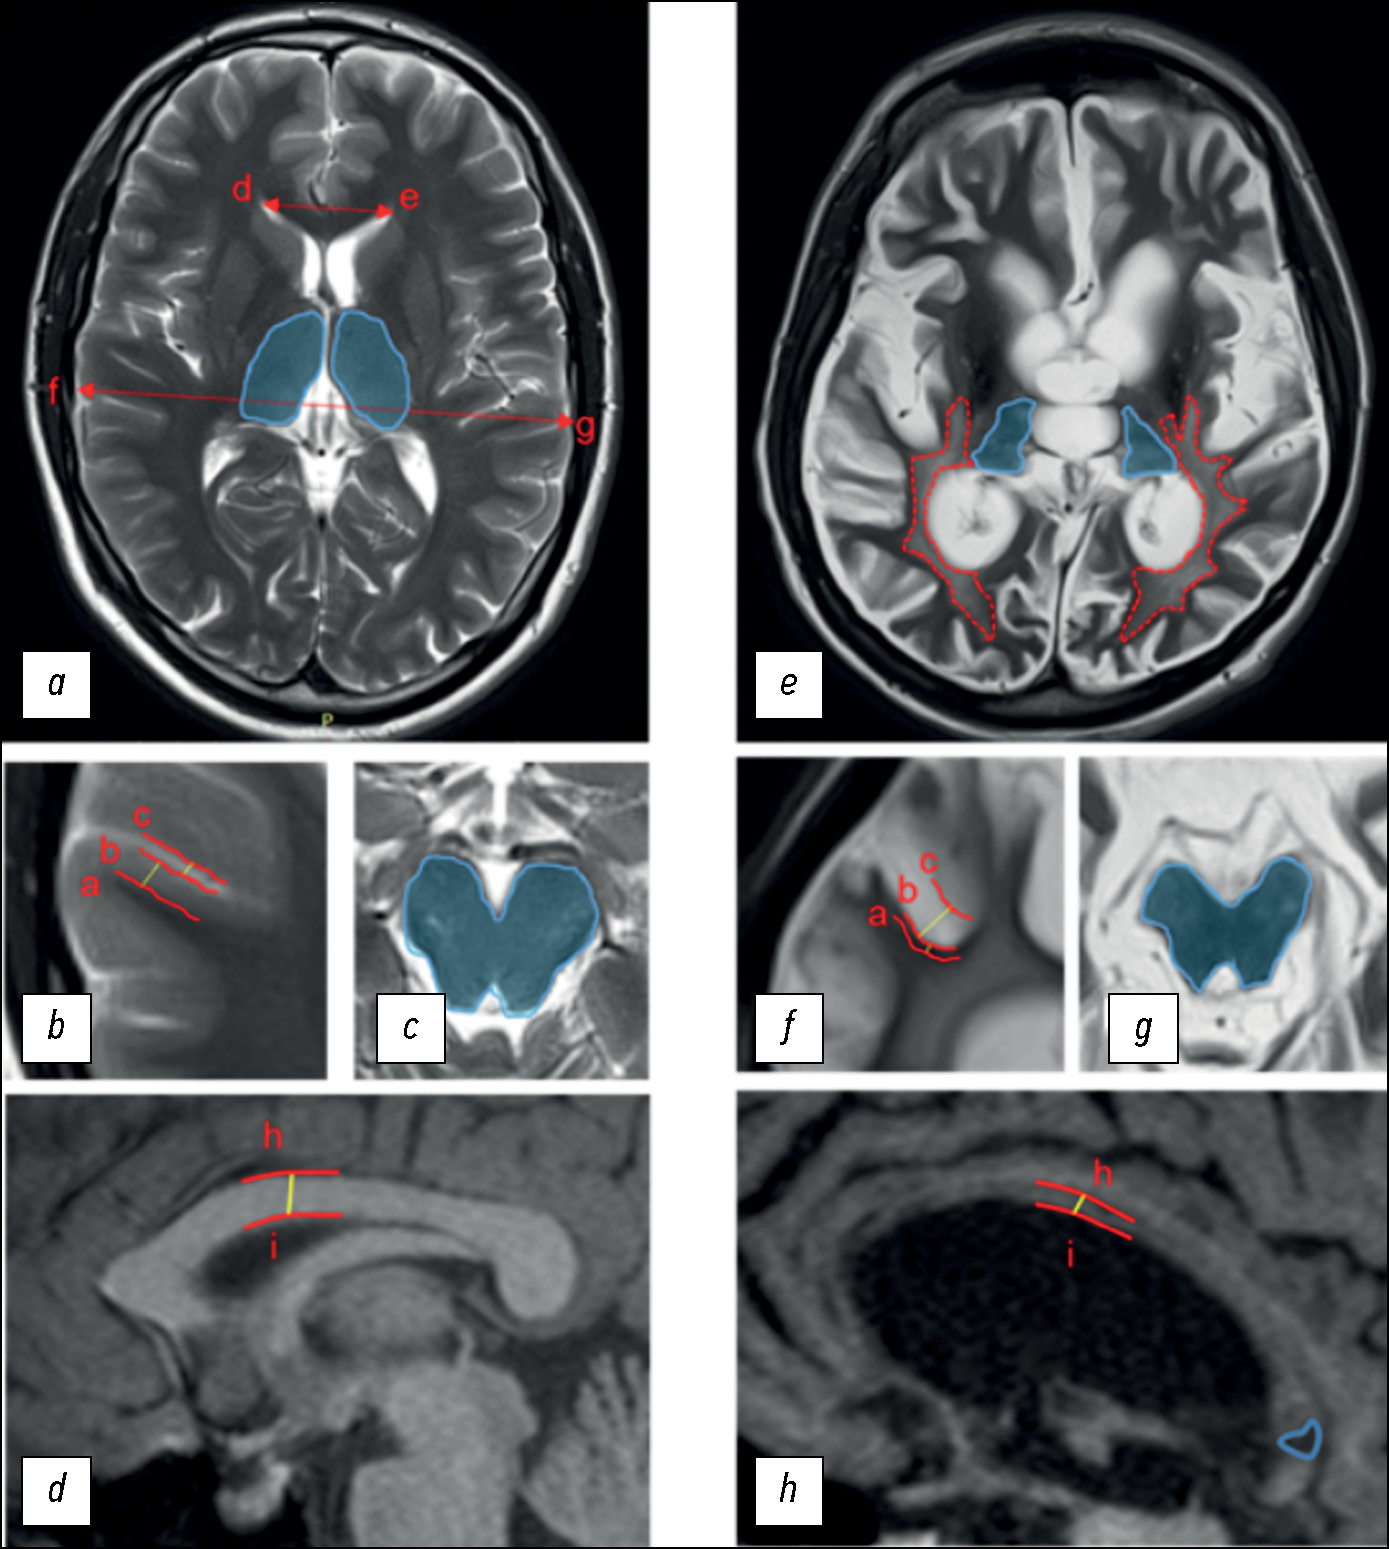

To assess structural changes according to DOC-MRIDS, the most commonly reported indicators were selected, including diffuse cortical atrophy, ventricular enlargement, sulcus widening, leukoaraiosis, degeneration of the brain stem and/or thalamus, corpus callosum degeneration, and focal lesion of the corpus callosum (Fig. 1).

Fig. 1. Disorders of Consciousness MRI-Based Distinguishing Scale (DOC-MRIDS) score: (a–d) in a healthy volunteer; (e–h) in a CDoC patient. Specified distances: (a–b) cortex thickness; (b–c) sulcus width; (h–i) thickness of the central part of the corpus callosum; distances (d–e; f–g) were used to calculate the Evans index. Blue areas: (a) unchanged thalami; (c) brain stem; (e) thalamic degeneration; (g) brain stem degeneration. Lines: (e) red dotted lines represent the extent of leukoaraiosis; (h) the solid blue line corresponds to hypointense lesions in the corpus callosum.

In diffuse cortical atrophy, brain stem and/or thalamus degeneration, and corpus callosum damage, the changes were classified as the presence (1) or absence (0) of pathology. Confirmed extensive cortical thinning and symmetrical bilateral decrease in thalamic and/or brain stem size were considered. Unilateral damage due to stroke or injury was considered to be the absence of the sign. The remaining parameters were assessed as follows: 0 = no changes; 1 = moderate changes; 2 = severe changes:

- moderate and severe ventricular enlargement corresponded to the Evans index of 0.31 to 0.74 (1) and >0.74 (2), respectively;

- subarachnoid space enlargement of 0.2–0.4 cm was classified as moderate sulcus widening (1) and of >0.4 cm as severe sulcus widening (2);

- periventricular caps and diffuse periventricular changes in the signal intensity in the white matter were classified as moderate leukoaraiosis (1); large, confluent T2 hyperintense areas extending to deep white matter and the subcortex were classified as severe leukoaraiosis (2);

- corpus callosum degeneration was assessed by the thickness of its central part: 0.4–0.2 cm for moderate degeneration (1) and <0.2 cm for severe degeneration (2).